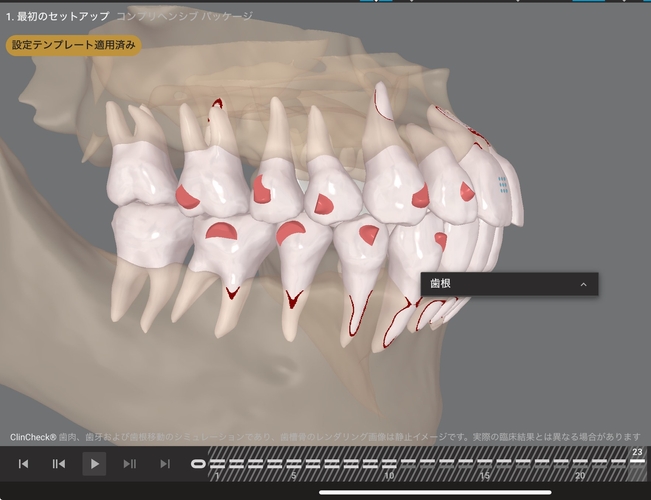

添付のシミュレーション画像(※別の患者の症例)では、右がAIによる自動提案プラン、左が歯科医師の診断を踏まえて調整した治療計画を示している。

画像下に表示されている数字は、使用するマウスピースの枚数を示しており、1枚あたりの装着期間は一般的に約7〜10日とされている。

AIによる提案は治療計画の目安として有効である一方、患者の主訴を丁寧に聞き取り、歯科医師が歯の動きや噛み合わせ、歯根・歯槽骨の状態まで考慮して調整を行うことで、使用するマウスピースの枚数が減り、結果として治療期間が短縮されるケースも見られる。

AIによるシミュレーション(23ステージ)